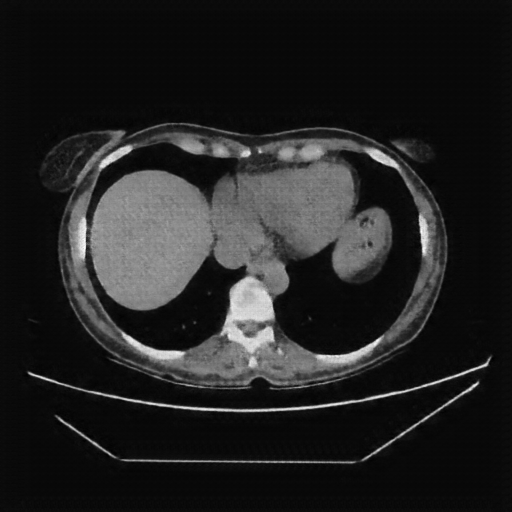

Generated VENOUS CT scan (A→B translation)

Full window (WL 1023.5, WW 4095 β†’ Low βˆ’1024, High +3071)

Actual HU range: [-811.5, 753.5]

Lung window (WL -600, WW 1500 β†’ Low βˆ’1350, High +150)